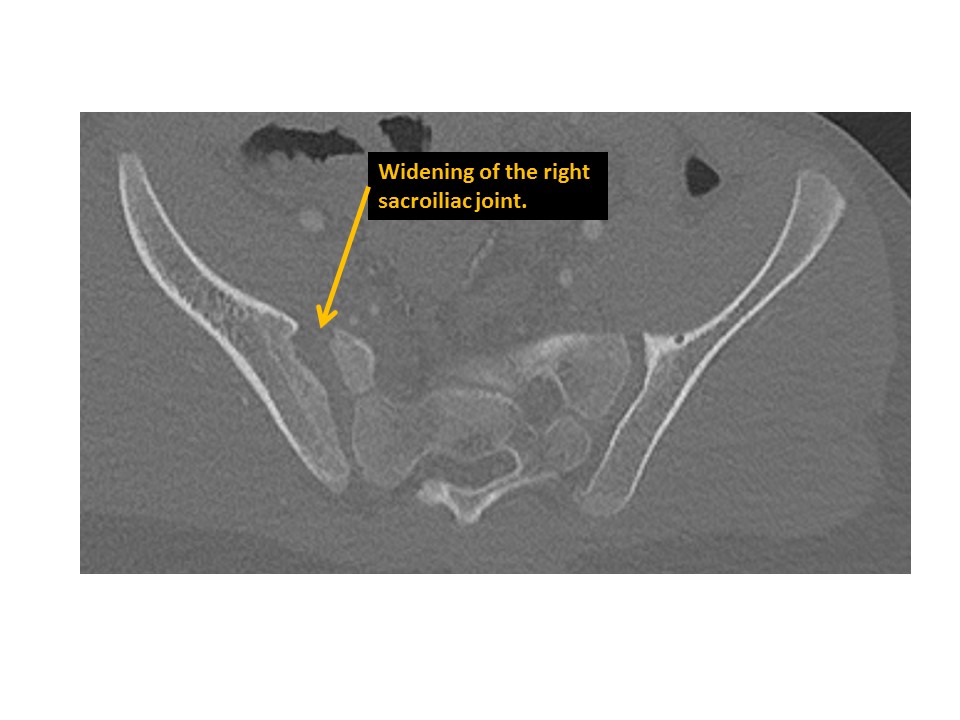

SACRUM and SACROILIAC JOINTS

The sacroiliac joints are widened and asymmetric. [Yes/No]

There is vertical subluxation of the sacroiliac joints. [Yes/No]

There are CT findings of sacroiliac inflammation or degeneration. [Yes/No]